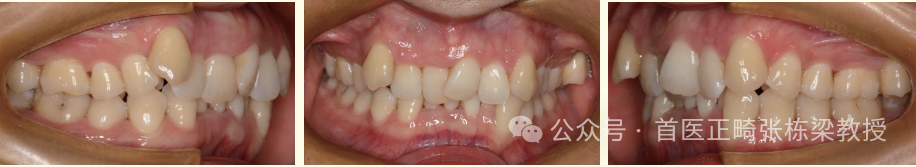

就像这位女士主诉深咬合、前牙拥挤,除此之外,临床检查牙根尖片检查见前牙牙根吸收。

因此如何帮助女士排齐前牙,打开咬合,保持前牙不松动,还要保持面型良好,这是牙齿矫正的目标。

考虑到牙齿牙根和面型问题,我们设计不拔正畸牙的牙齿矫正方案,升高后牙解除前牙咬合创伤,这也是确保牙根不再吸收加重的关键点。